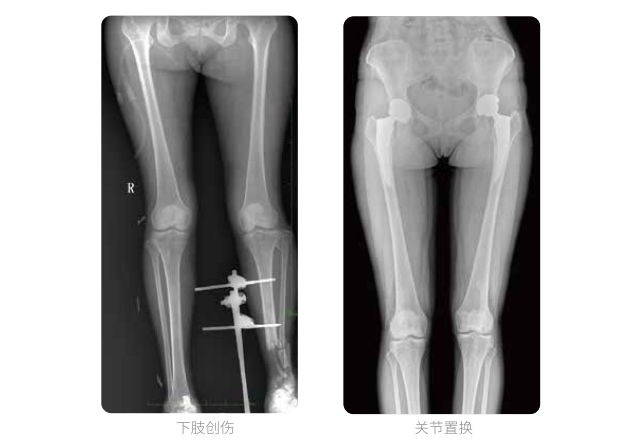

双下肢临床影像

髓内钉手术是骨科、手足外科中常见的微创型手术方式,患者随访时需拍摄置入在股骨、肱骨处的较长髓内钉。PLX8600视野拍摄,能够出色解决医生需多次摄影再拼接的痛点。一次成像双下肢,即拍即得,高效率,无需拼接。工作站软件自带的测量功能方便医生读取双下肢长度数据,助力准确诊断。

动态DR所具备的全脊柱、全下肢全景成像技术检查,能够更加清晰的显示患者病情变化情况,对骨科疾病患者的全脊柱、全下肢病变情况图像展示更加具有完整性,对患者在自然状态下的应力情况展示较为全面,有助于骨科疾病患者临床诊断效果的提升,对患者临床治疗方案的科学制定有着积极的作用。